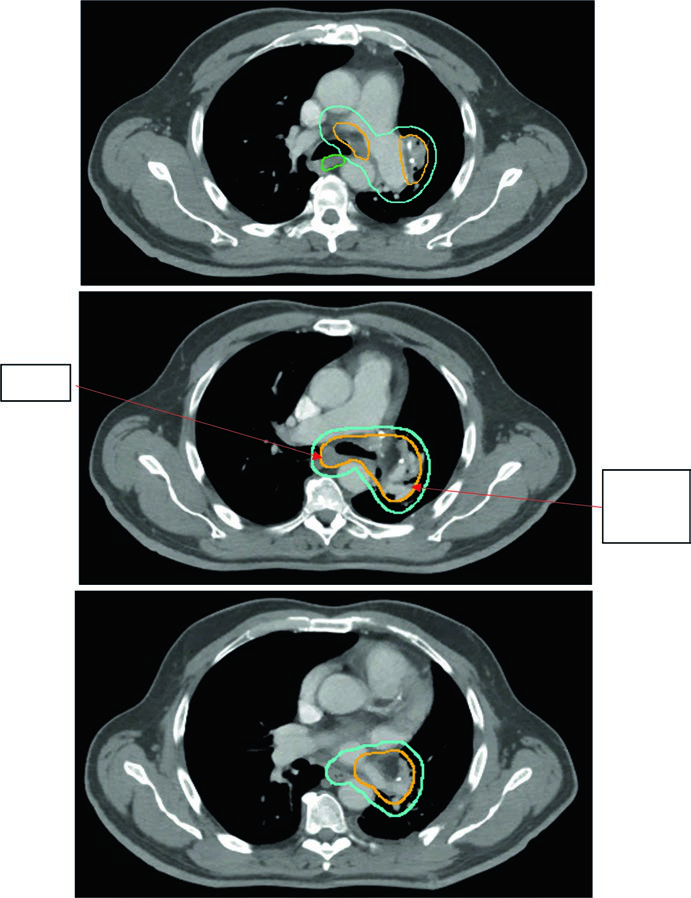

A dose máxima em ponto da PBT é restrita a 55 Gy em qualquer esquema. A Figura 13.2 do texto mostra três casos de estádio inicial: tumor periférico clássico tratado com 54 Gy/3fx, tumor próximo à PBT com 48 Gy/4fx e tumor central com 50 Gy/5fx.

A expansão iGTV → iCTV no estádio inicial é pequena: 0 a 0,2 cm. O raciocínio é que, no tumor pequeno e periférico, a extensão microscópica é mínima e a margem de setup domina a expansão final. A margem PTV adicional depende da tecnologia de IGRT disponível.

A árvore brônquica proximal (PBT) — definida como os 2 cm distais da traqueia, carina, brônquios principais, brônquios lobares e os primeiros segmentos dos brônquios segmentares — é a estrutura mais crítica no SBRT. Define-se uma zona de não irradiação (NFZ) de 2 cm além da PBT. Tumores dentro ou adjacentes à NFZ são considerados centrais e demandam fracionamento menos ablativo.

Os esquemas de dose variam por localização:

- Periférico: 54 Gy/3fx (18 Gy/fx), 48 Gy/4fx (12 Gy/fx), 50 Gy/4fx ou 50 Gy/5fx

- Central: 50 Gy/5fx, 70 Gy/10fx ou 60 Gy/8fx